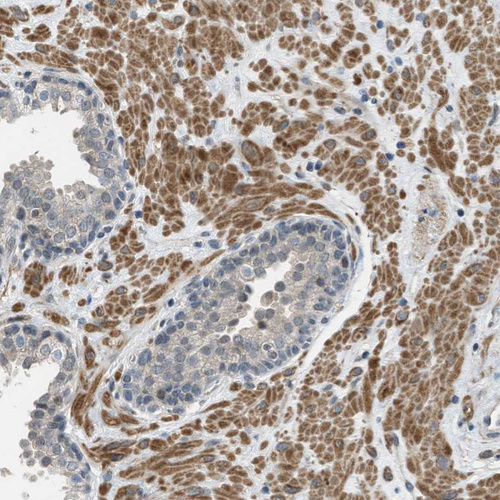

Immunohistochemical staining of human testis shows weak to moderate cytoplasmic positivity in cells in seminiferous ducts.